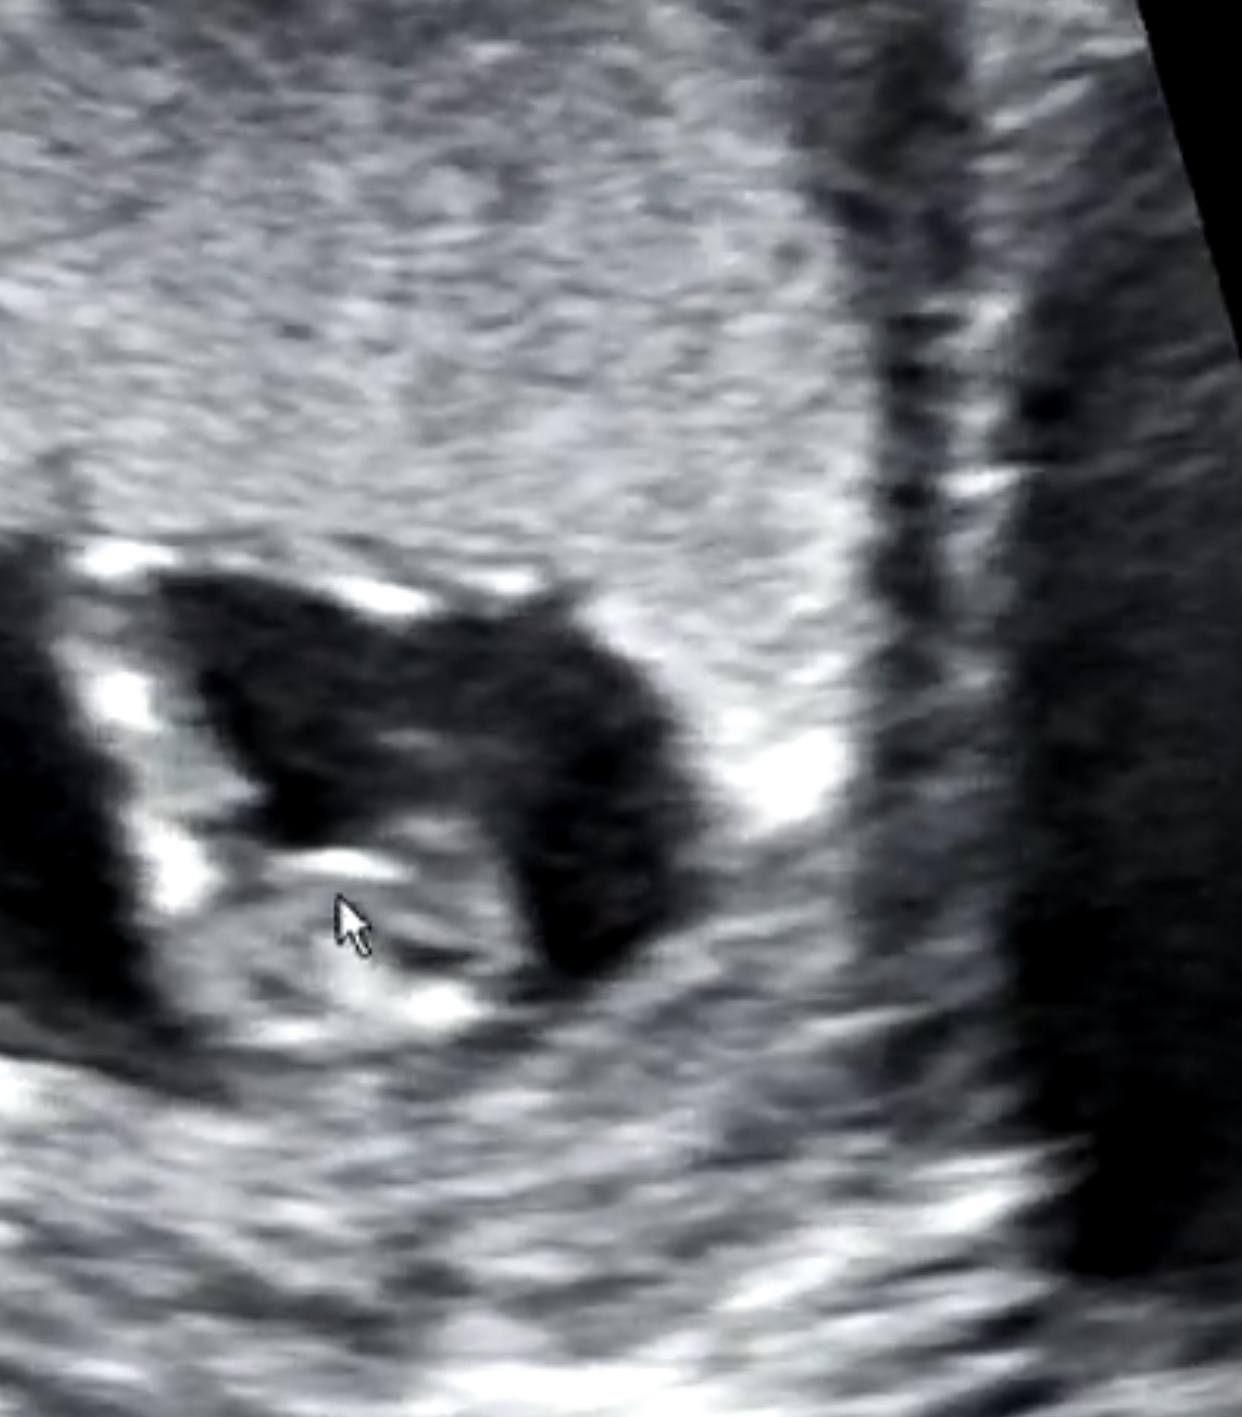

I am so anxious here! We went to the doctor yesterday for my 13 week scan and the doctor said he knew the grnder, but my husband doesn’t want to knooow! (So frustrating) we have 2 boys and want to know if I need to buy things or recycle!!

I will appreciate your help!!Attachment 40938Attachment 40939Attachment 40940